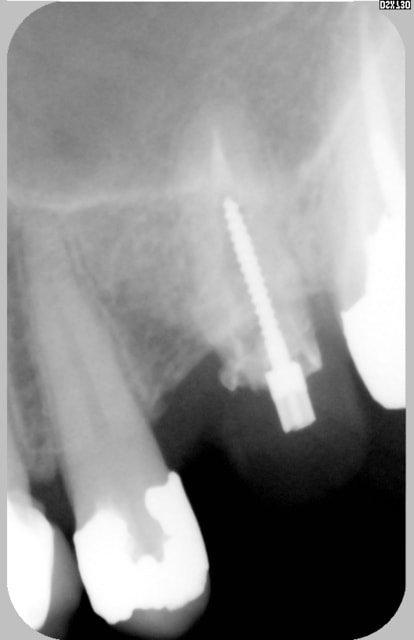

comme Sbire en moins mieux...

Prov n attente zwlcs1 - Eugenol

Provisoire kaipan - Eugenol

la 25 donc, pis apres ré-endo de ce qui reste de 26 pis apres la fixe def, mais plus tard...

j'avais un autre cas mieux et terminé depuis queques années, mais sais plus ou il est...

Prepa25 y7xacl - Eugenol